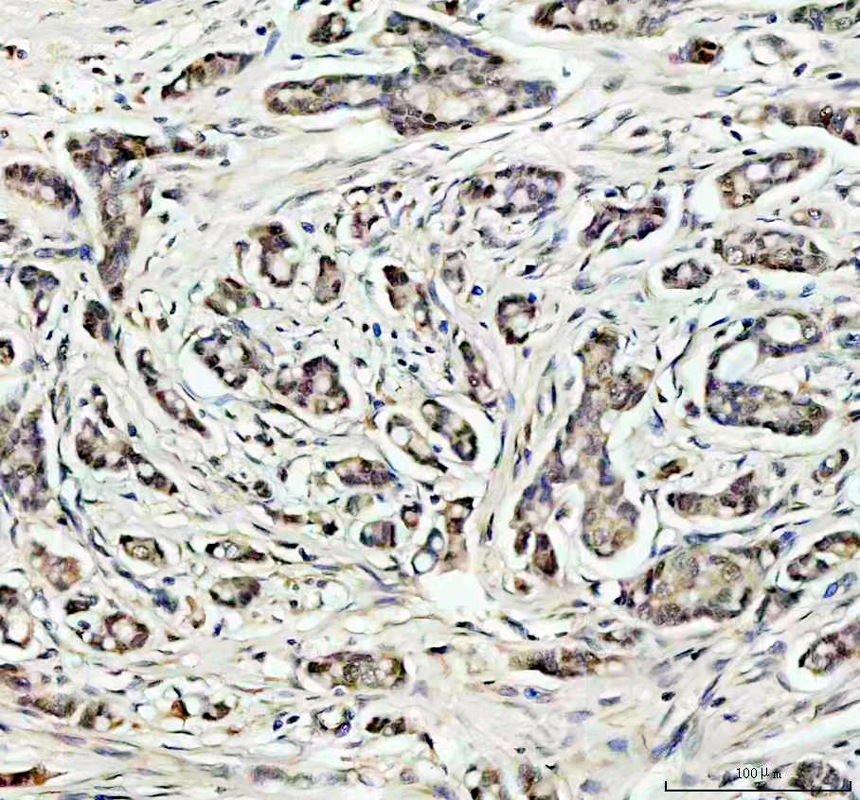

• IHC analysis of SOD1 using anti-SOD1 antibody (PB0453).

SOD1 was detected in a paraffin-embedded section of human breast cancer tissue. The tissue section was incubated with rabbit anti-SOD1 Antibody (PB0453) at a dilution of 1:200 and developed using HRP Conjugated Rabbit IgG Super Vision Assay Kit (Catalog # SV0002) with DAB (Catalog # AR1027) as the chromogen.